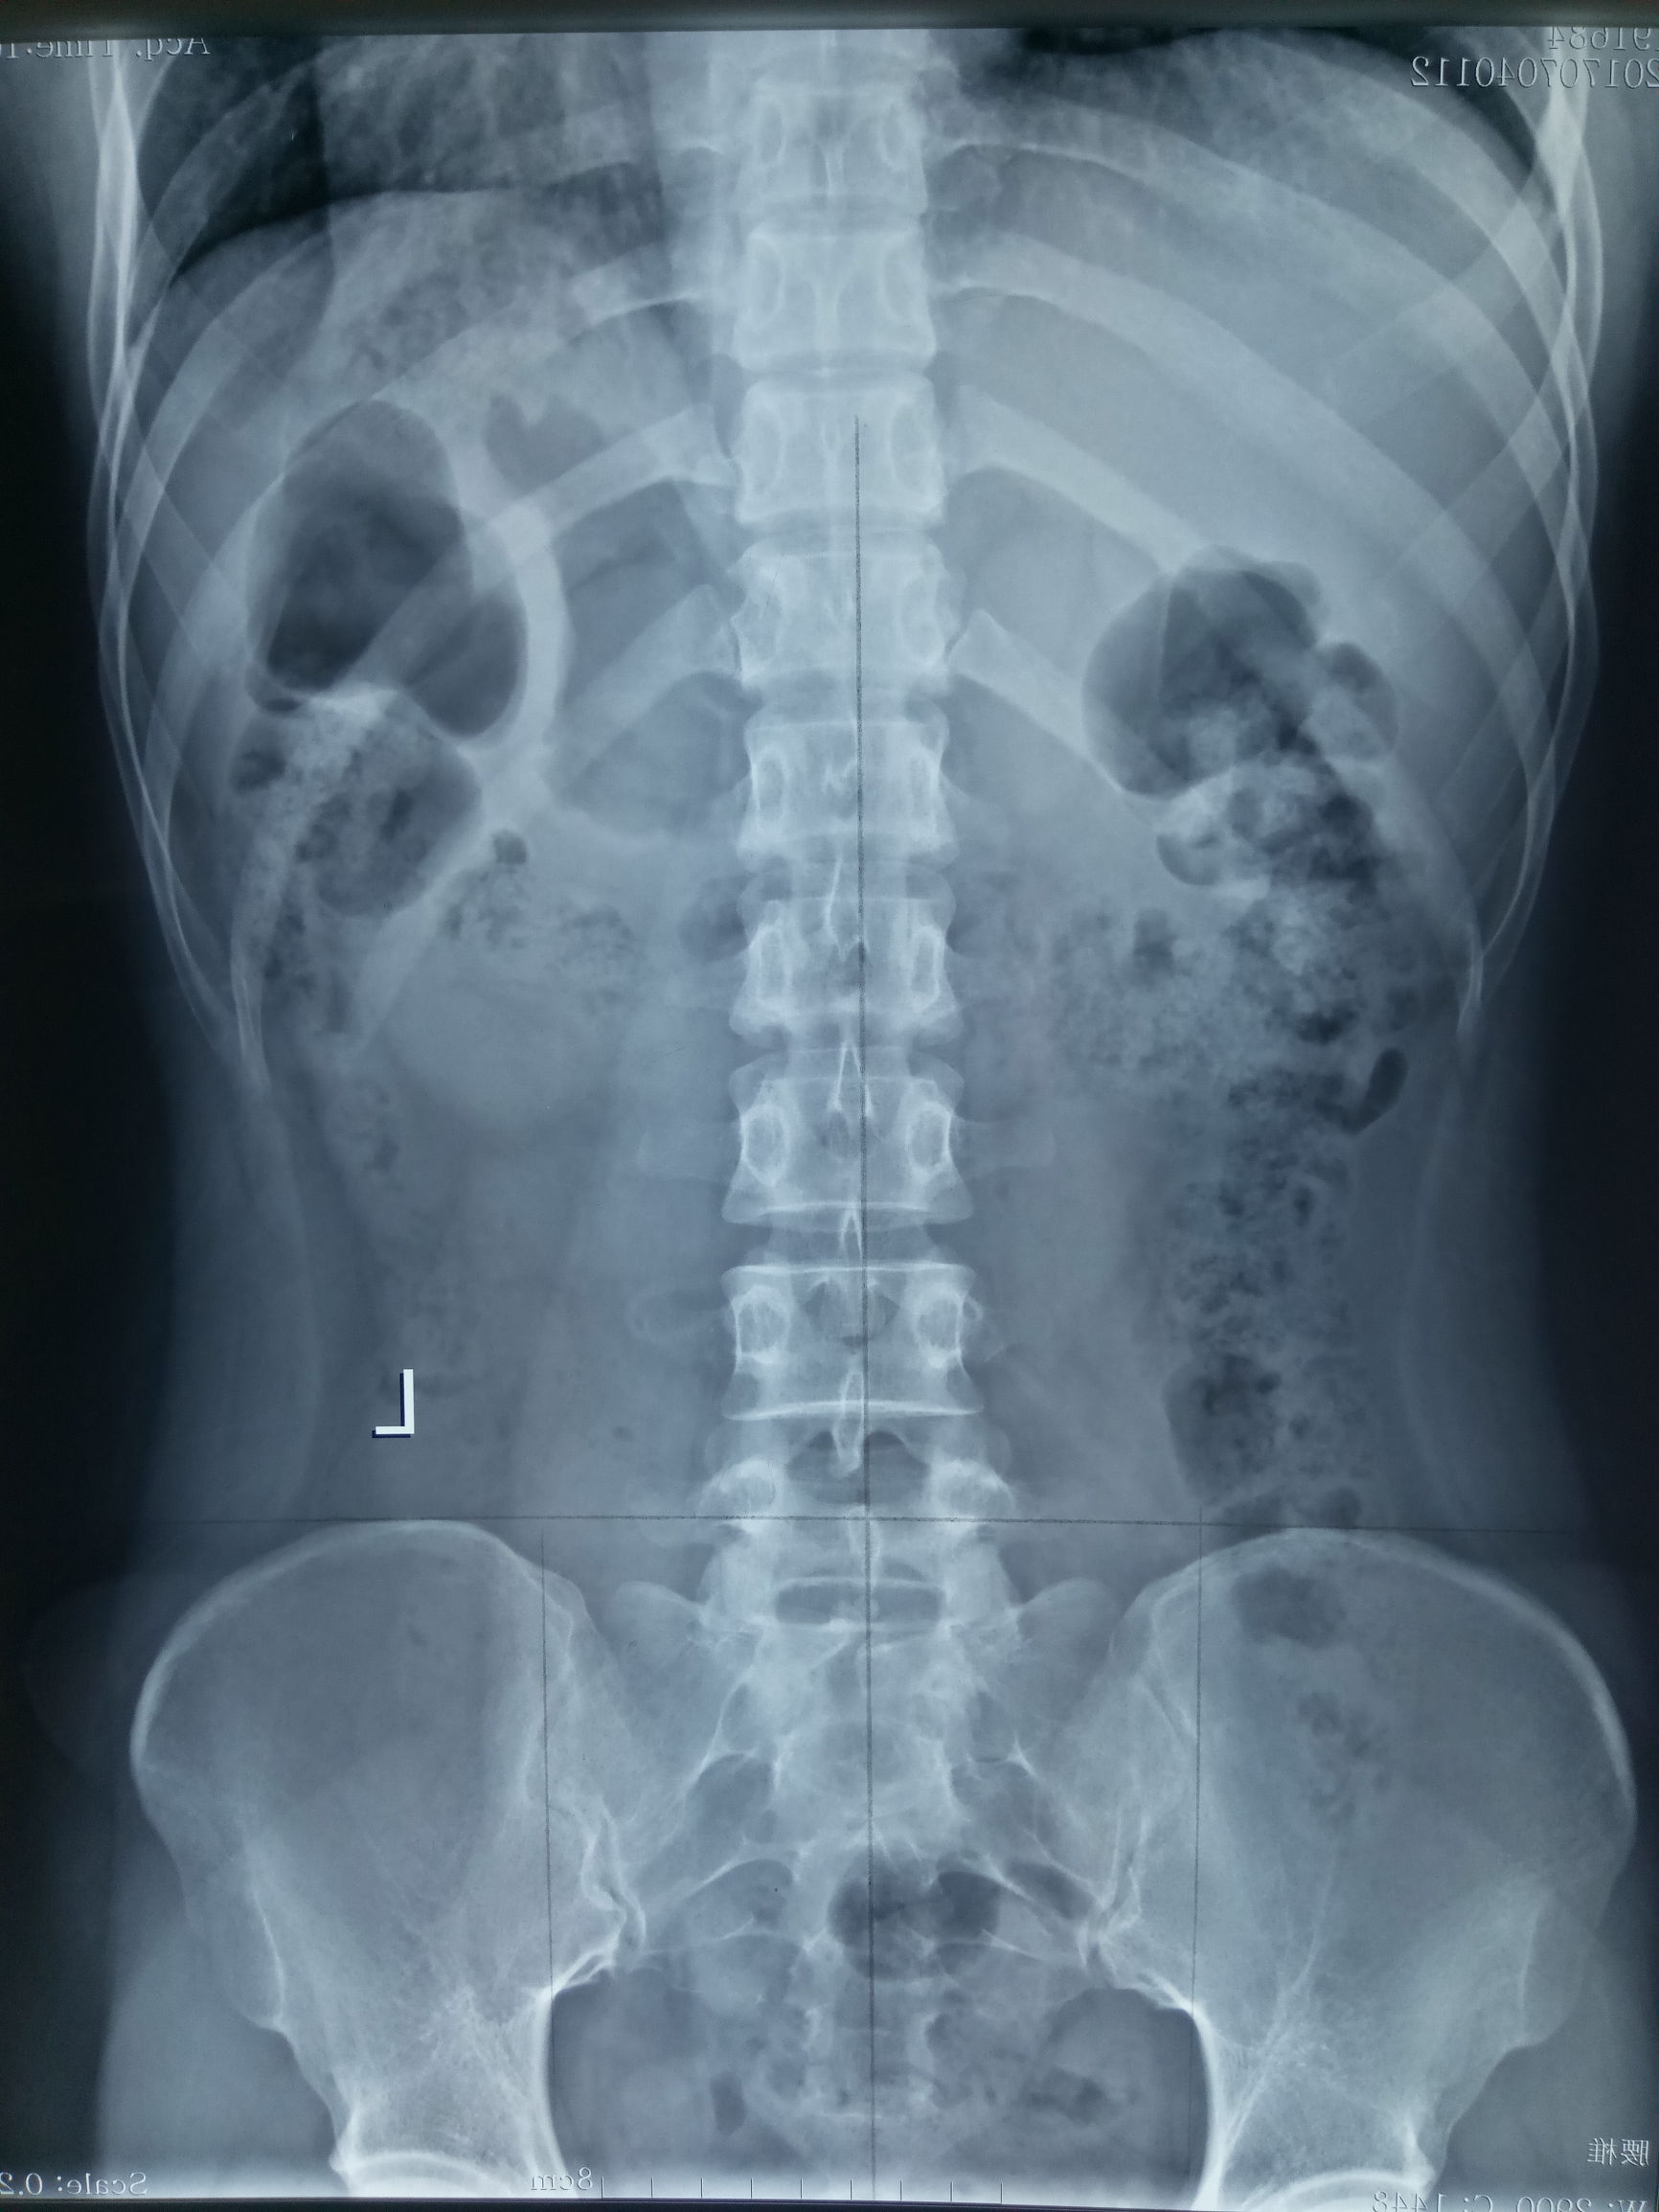

治疗过程:经过三次矫正后,昨日顾客又拍片子,如下。

此时可以看到,腰椎侧弯已经明显好转,双侧髂骨基本同高,骶骨倾斜好转。腰4、腰5旋转恢复。

病案分析:这就是很典型的骨盆病变导致的腰椎侧弯变形的案例。因为骨盆是脊柱的底座,相当于高楼大厦的地基,地基不稳,大厦将倾,这是很简单的道理。所以治疗脊柱变形时,一定要注重骨盆的矫正,恢复地基稳定,大楼自然不倒。附上对比图如下: